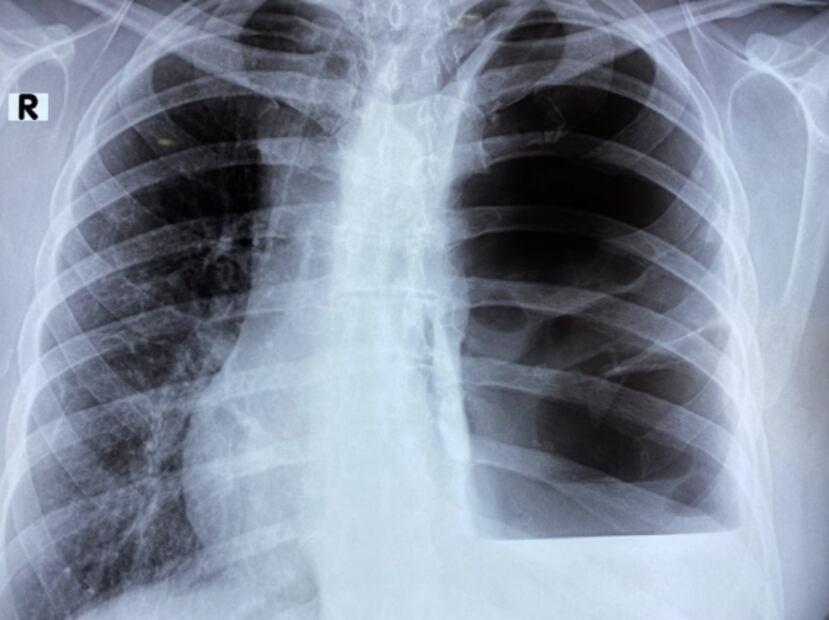

Un científico del Instituto Politécnico Nacional (IPN) destacó la importancia de la atención médica temprana, luego que a través del análisis ha sido posible apreciar cambios pulmonares en pacientes asintomáticos y con pruebas negativas de detección del coronavirus SARS-CoV-2 , que provoca la enfermedad Covid-19 .

Guillermo Prado Villegas señaló a través de un comunicado que es importante, además de la atención médica temprana, contar con estudios de tomografía del tórax, imprescindible para la detección de la enfermedad que ha provocado más de 82 mil fallecimientos en México .

El investigador de la Escuela Superior de Medicina (ESM) reconoció que pese a la negativa que arrojen pruebas de Reacción en Cadena de Polimerasa (PCR), las tomografías son de gran utilidad pues demuestran el daño generado por el coronavirus.

Respecto a las afecciones en personas asintomáticas apuntó que estos pacientes repentinamente presentan dificultad para respirar y en algunos casos fibrosis o necrosis del parénquima pulmonar.

“Hay personas que creen tener un cuadro faríngeo, gripe o tos habitual, cuando realmente cursan con una enfermedad grave y ya tienen neumonía, destrucción del tejido pulmonar, bullas (espacios que carecen de pared epitelial), neumotórax, abscesos o paquipleuritis y diversos grados de fibrosis pulmonar”, puntualizó el experto de la Unidad de Terapia Intensiva Covid del Centro Médico Nacional "La Raza".

Prado Villegas dijo que es importante tratar de forma temprana la neumonía atípica, esto para contener la gravedad de los daños ocasionados por la afección.